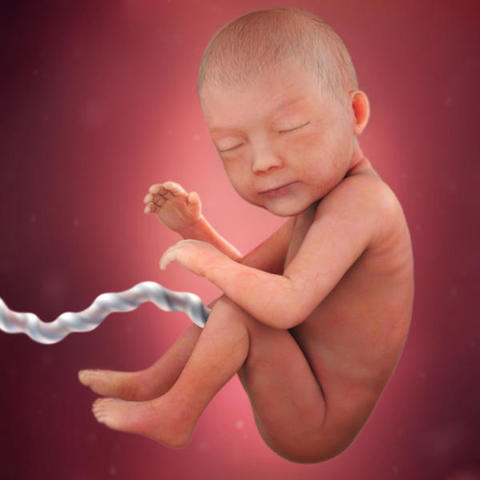

• Semana 40 - Termina Tercer Trimestre - Hora del parto

Semana 40 - Termina Tercer Trimestre - Hora del parto

Ahora el bebé pesa alrededor de 3 o 3,5 kilos y su longitud oscila entre los 49 y los 53 centímetros. Tiene unas uñas muy largas.

El interior del tubo digestivo del bebé se rellena de meconio: una pasta verdosa, formada por pigmentos biliares, productos de la secreción y descamación del tubo digestivo y restos deglutidos del líquido amniótico.

En su 40ª semana del embarazo, van 38 semanas desde la concepción y su bebé podría nacer en cualquier momento.